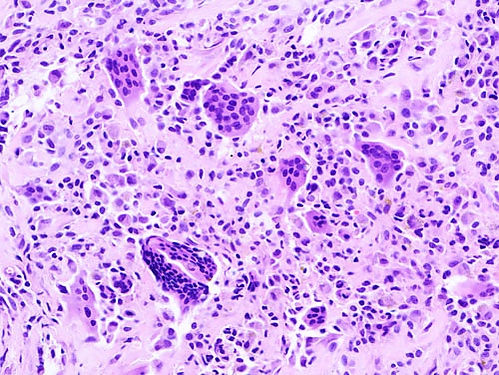

После удаления опухоли все патологические ткани направляются на морфологическое исследование. Микроскопическая картина опухоли характеризуется обилием гемосидерина, скоплениями гигантских многоядерных клеток и гиперплазией прилежащей синовиальной оболочки. Кроме того, в опухоли встречаются гистиоцитоподобные клетки, синовиальные фибробласты, лимфоциты и мелкие кровеносные сосуды разного калибра[3].